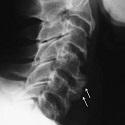

La maladie de Forestier : une cause rare de dysphagie à ne pas méconnaître

Wassia Kessomtini, Wafa Chebbi

PAMJ. 2014; 18: 140. Published 17 June 2014